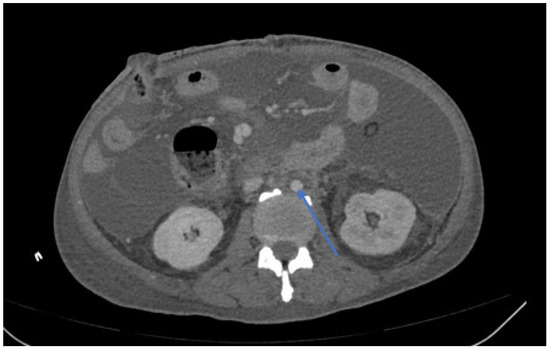

| Peri-graft/retroperitoneal abscess | 21 (48%) |

| Graft duodenal fistula | 10 (23%) |